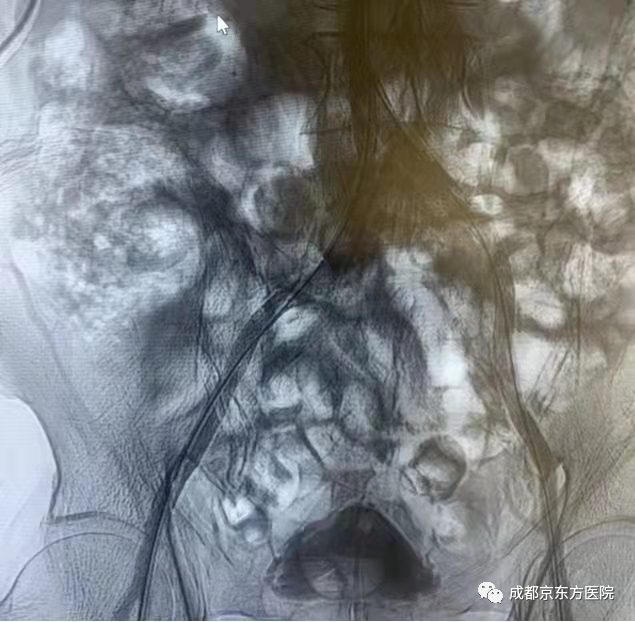

术前造影图像

姜大春主任组织全院MDT会诊后,制定了严密的手术方案。手术团队经不懈努力,成功进行了双侧股动脉无搏动下盲穿,左侧肱动脉穿刺,腹主动脉造影,双侧髂动脉造影,双侧髂动脉球囊扩张+外周血管支架植入术。手术团队谨慎每一步操作,最终实现股动脉入路导丝与肱动脉入路导丝的双向血管内膜下的真腔会师,历时2小50分,克服重重困难打通闭塞的血管,经进行球囊扩张,分别在左、右侧髂动脉植入外周血管自膨胀支架。术后复查造影效果满意,左、右侧髂动脉显影良好,双侧股动脉明显触及波动。次日,患者双下肢血运改善,行走不适感明显消失。